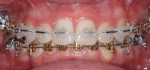

Behandlung mit weißen (zahnfarbenen) Brackets und goldenen Brackets

Die auf die Zähne geklebten Brackets sind in der Regel aus Stahl und daher silberfarbig. Stählerne Brackets sind besonders schlank und bieten eine sehr exakte Führung für die aktiven Elemente der Zahnspange. In manchen Fällen ist es auf Grund der beruflichen Situation des Patienten nötig, möglichst unauffällige, also zahnfarbene Brackets zu verwenden.

Auch die Verwendung goldfarbiger Brackets (und zum Teil auch Drähte) ist möglich und verbessert oft entscheidend die kosmetische Wirkung. Die Qualität derartiger goldfarbener Brackets ist dabei ähnlich gut wie die der silbernen.

Besonders elegant ist die Verwendung einer Kombination zahnfarbener und goldfarbiger Brackets.